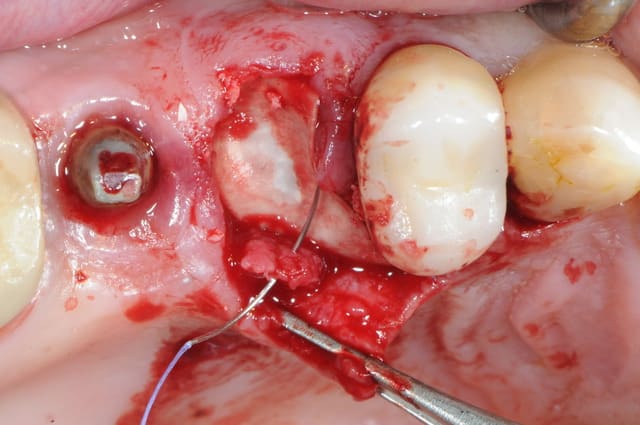

Patiente présente une perte alvéolaire de la table externe suite à fracture radiculaire.

J'ai réalisé un lambeau tracté coronairement mais je pense que certains auraient peut-être réalisé un lambeau conjonctif palatin.

Il manque juste une photo de la membrane biogide que je ne retrouve pas.